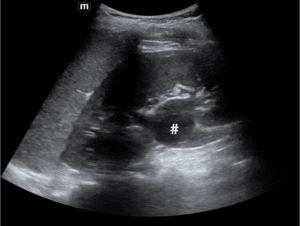

In the meantime, d-dimer concentrations were found to be 1840 ng/mL and therapeutic anticoagulation with Enoxaparin 1 mg/kg every 12 hours was initiated. Computed tomography (CT) of the chest, abdomen, and pelvis with contrast revealed findings consistent with May-Thurner syndrome, with the left and right common iliac arteries compressing the left iliac vein proximal to the clot (Figure 4).

Figure 4 Contrast-enhanced CT showed that the left iliac vein (arrowhead) was compressed by the left and right common iliac arteries (asterisk), consistent with a diagnosis of May-Thurner syndrome.